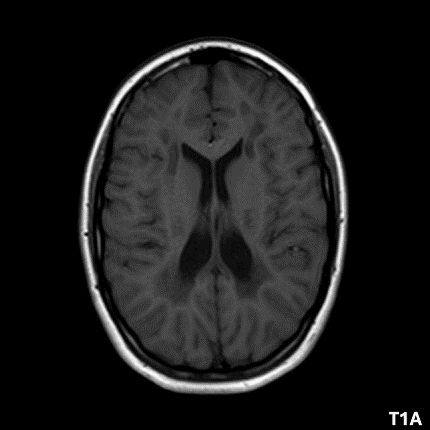

- A) Aksiyel T2A ve koronal T2A sekanslarda sentrum semiovale, korona radiata ve bazal ganglionlar düzeyinde bilateral frontoparietal derin periventriküler beyaz cevherde birleşme eğilimi gösteren hiperintens gliotik sinyal değişiklikleri (oklar) ve aksiyel T2A serilerde servikal spinal kordda posterior kolonda, lateral kesimlerde sinyal artımları (oklar) izlendi.

- B) Kontrastsız T1A serilerde tarifli alanlarda hipointens (oklar) görünüm izlendi. Kontrastlı T1A serilerde bu düzeyde (oklar) kontrastlanma artışı izlenmedi. Diffüzyon ağırlıklı serilerde belirgin diffüzyon kısıtlaması (oklar) görülmedi.

- LBSL, karakteristik radyolojik özelliklere sahiptir. MRG’de tipik olarak bilateral ve simetrik beyaz cevher sinyal değişiklikleri görülürken, subkortikal U lifleri, internal kapsülün posterior kolları, trigeminal sinir traktları, serebellum, korpus kallozumun spleniumu, medulla oblongata ve omurilikteki dorsal kolonlar ile lateral kortikospinal traktlar genellikle korunur.

- Etkilenen bölgelerde T1’de hipointens, T2/FLAIR’da hiperintens sinyal değişiklikleri izlenir. DWI’de lezyonların periferinde kısıtlı difüzyon görülebilir. MRS’de beyaz cevherde laktat artışı saptanabilir, ancak bu her hastada mevcut değildir.